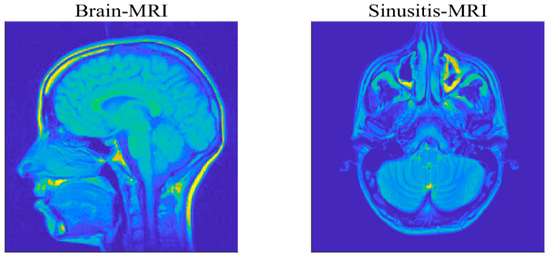

(2) Magnetic Resonance Imaging Example

To further verify the effectiveness and practicability of the proposed algorithms, this part will focus on the reconstruction of medical images. The used MRI images are of size 256 × 256 , for a brain MRI and sinusitis MRI, as shown in Figure 12, and evaluate the recovery performance by the value of PSNR. We utilize the Haar wavelets as the basis for sparse representation of the images. The compression ratio M/N is set as 0.4 and the measurement matrix is a partial DCT matrix. A Gaussian mixture model (GMM) ( f = ρ N ( 0 , σ 2 ) + ( 1 ρ ) N ( 0 , k σ 2 ) ) is taken to model the impulsive noise, where the parameters ρ ( 0 , 1 ) and k > 1 respectively control the proportion and the strength of outliers in the noise [19]. To ensure fairness of comparison, the λ in each algorithm is selected by providing the best performance in terms of relative error of recovery [22].

Figure 12. Two test MRI images.